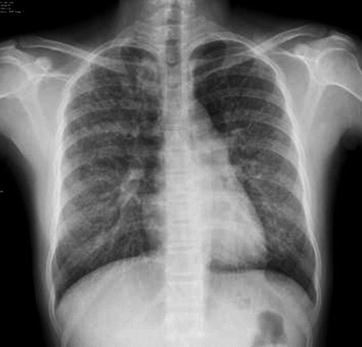

Typical measles pneumonia in children is mainly characterized by interstitial inflammation, with grid-like lung markings. The lesions are mainly distributed in both middle and lower lungs with accompanying small spots and flakes of blurry shadows (Fig. 23.3). The common changes also include widened right upper mediastinum, increased transparency of lung fields, and emphysematous changes. The incidence rate of enlarged and thickened hilar shadow is higher in children than in adults.

Fig. 23.3.

Pediatric measles pneumonia. At day 4 after hospitalization, X-ray demonstrates thickened and blurry pulmonary markings in both lungs, small grid-like shadow at the middle and medial parts of left upper lung, and flakes of blurry shadows at the right lower lung hilum